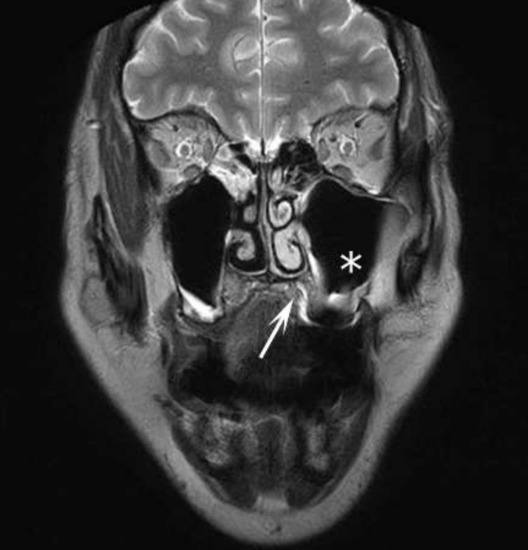

1.1. Case Report